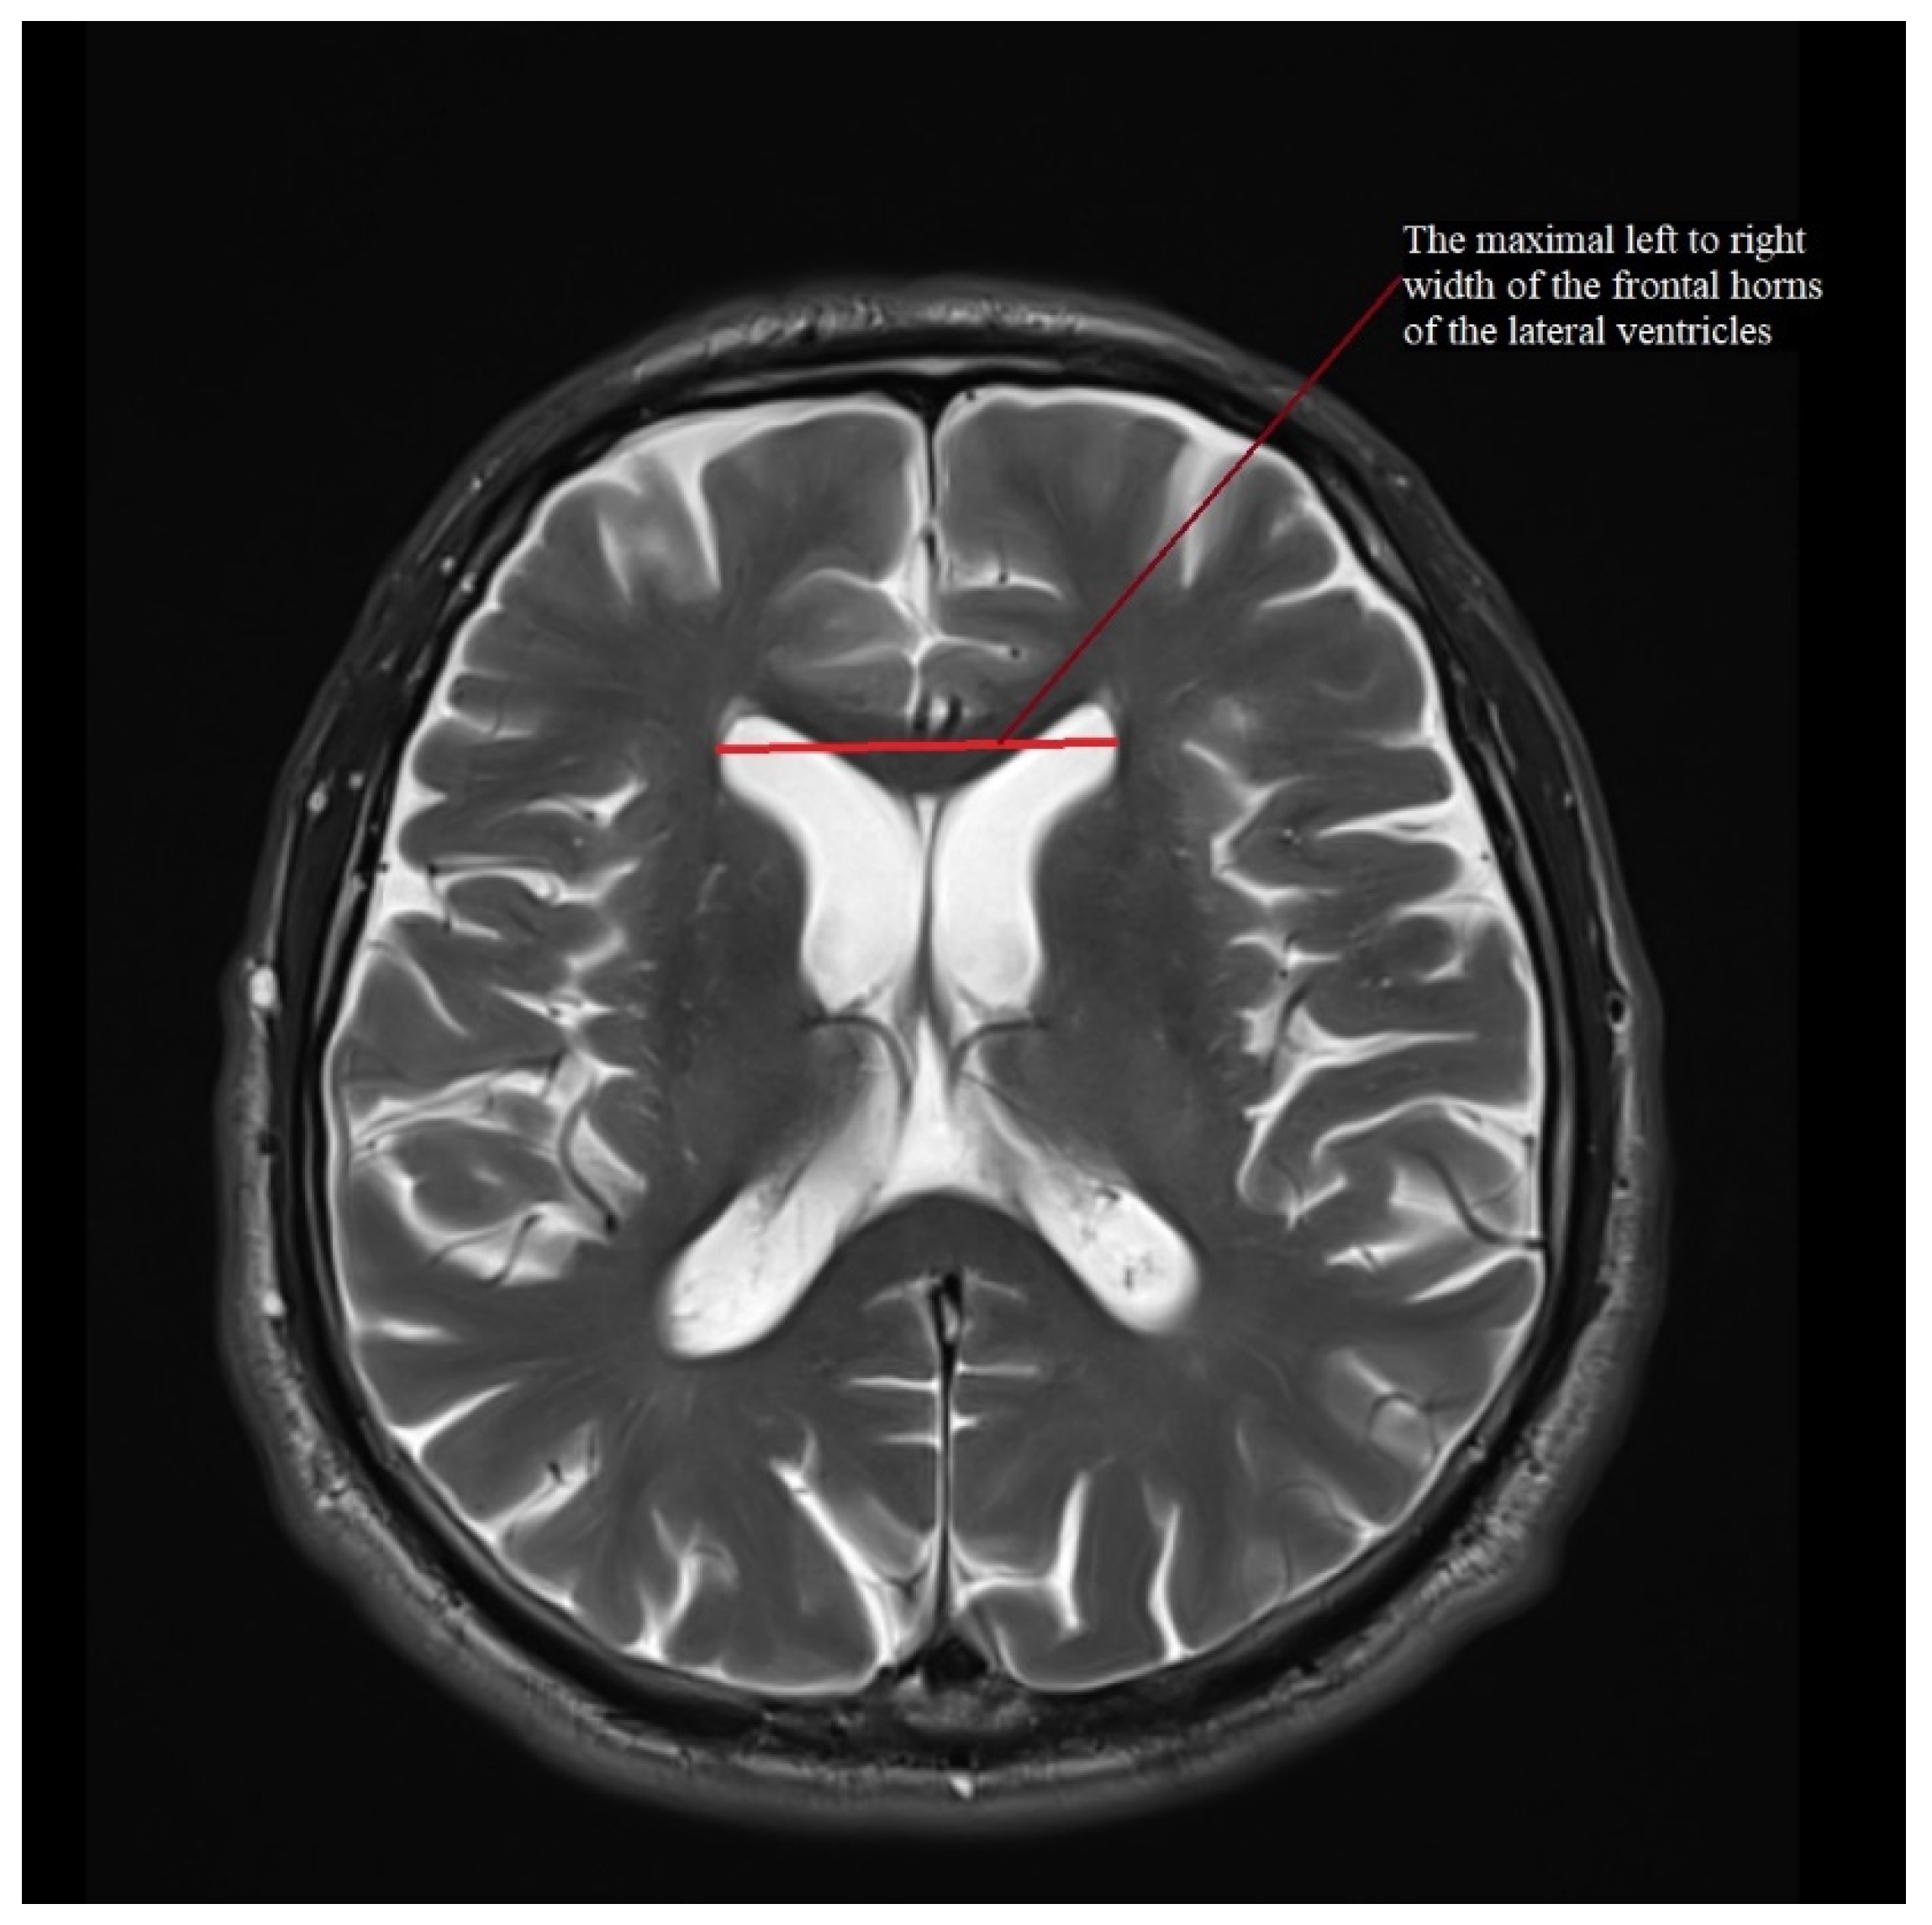

| III ventricle (mm) | 7.6 (4.2–12.5) | 2.2 ± 1.6–3.4 | 11.1 (6–16) | 2.5 ± 1.8–4 | 12.2 (5–19) | 3.1 ± 2.4–4.6 | 9.4 (6–14) | 2.5 ± 1.9–3.6 | 10.3 (7–14) | 2.1 ± 1.6–3.1 |

| MRPI | 11.247 (7.758–15.429) | 1.882 ± 1.39–2.912 | 17.384 (12.025–26.626) | 4.439 ± 3.183–7.327 | 19.366 (9.343–31.303) | 6.944 ± 5.247–10.27 | 10.766 (7.163–17.151) | 2.503 ± 1.915–3.614 | 15.363 (6.582–29.025) | 5.03 ± 3.801–7.439 |

| MRPI 2.0 | 2.342 (1.252–3.463) | 0.619 ± 0.457–0.958 | 4.338 (2.526–6.306) | 1.344 ± 0.964–2.219 | 5.646 (2.595–9.838) | 2.324 ± 1.756–3.436 | 2.558 (1.41–4.549) | 0.91 ± 0.696–1.314 | 4.195 (1.953–9.285) | 1.686 ± 1.274–2.493 |